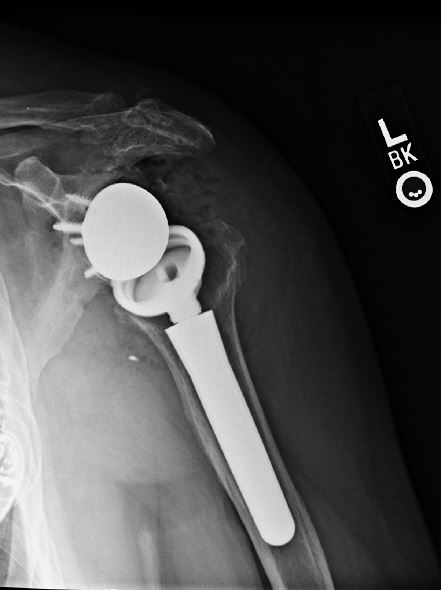

Total/Reverse Total Shoulder Replacement